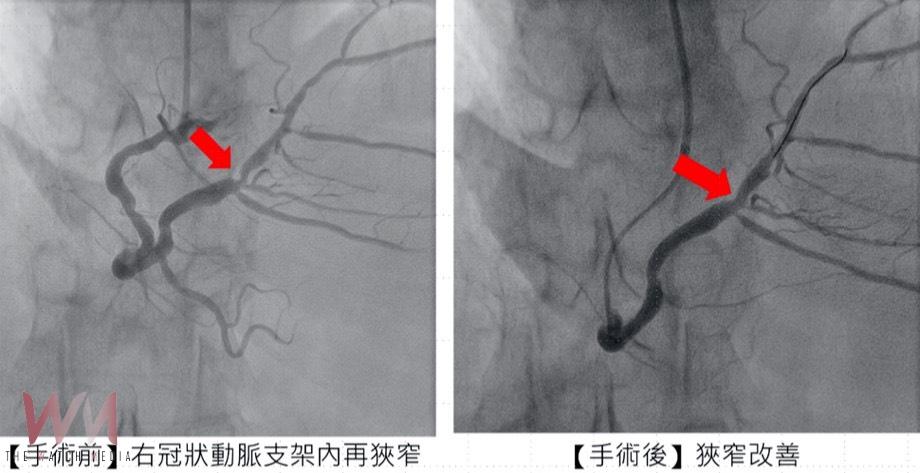

針對張先生的治療過程,市醫副院長兼心臟科專家陳建鈞醫師進一步說明,病人有多次支架再阻塞的病史,加上長途奔波與生活壓力,病情更加複雜。經團隊縝密評估後,決定採用「刀片氣球」及「塗藥氣球」治療,既能打通血管阻塞,也可降低再度狹窄的風險,大幅縮短康復時間。手術全程順利,患者隔日即可出院,術後更能安心規劃生活與健康管理。